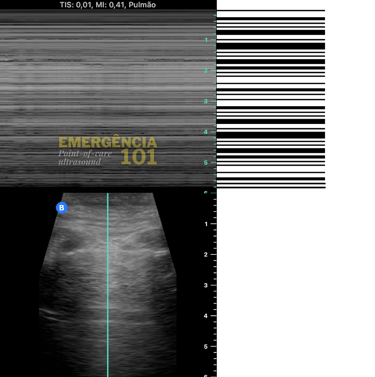

Em algumas situações, pode ser difícil visualizar se há ou não deslizamento pleural pelo modo B do ultrassom, como na avaliação dos ápices pulmonares, que são regiões naturalmente menos ventiladas, e/ou em pacientes com movimentos respiratórios menos intensos (imagine um paciente intubado com sedação profunda e volume corrente pequeno), nesses casos é possível utilizar o modo M (motion) do ultrassom para registrar o movimento da pleura, gerando dois sinais característicos:

Sinal da areia da praia: presença de deslizamento pleural. (figura 7b)

Sinal do código de barras: ausência de deslizamento pleural. (figura 7c)

Figura 7b. Seashore sign (Sinal da areia da praia no modo M), significando presença de deslizamento pleural no campo pulmonar avaliado. Acervo pessoal do autor.